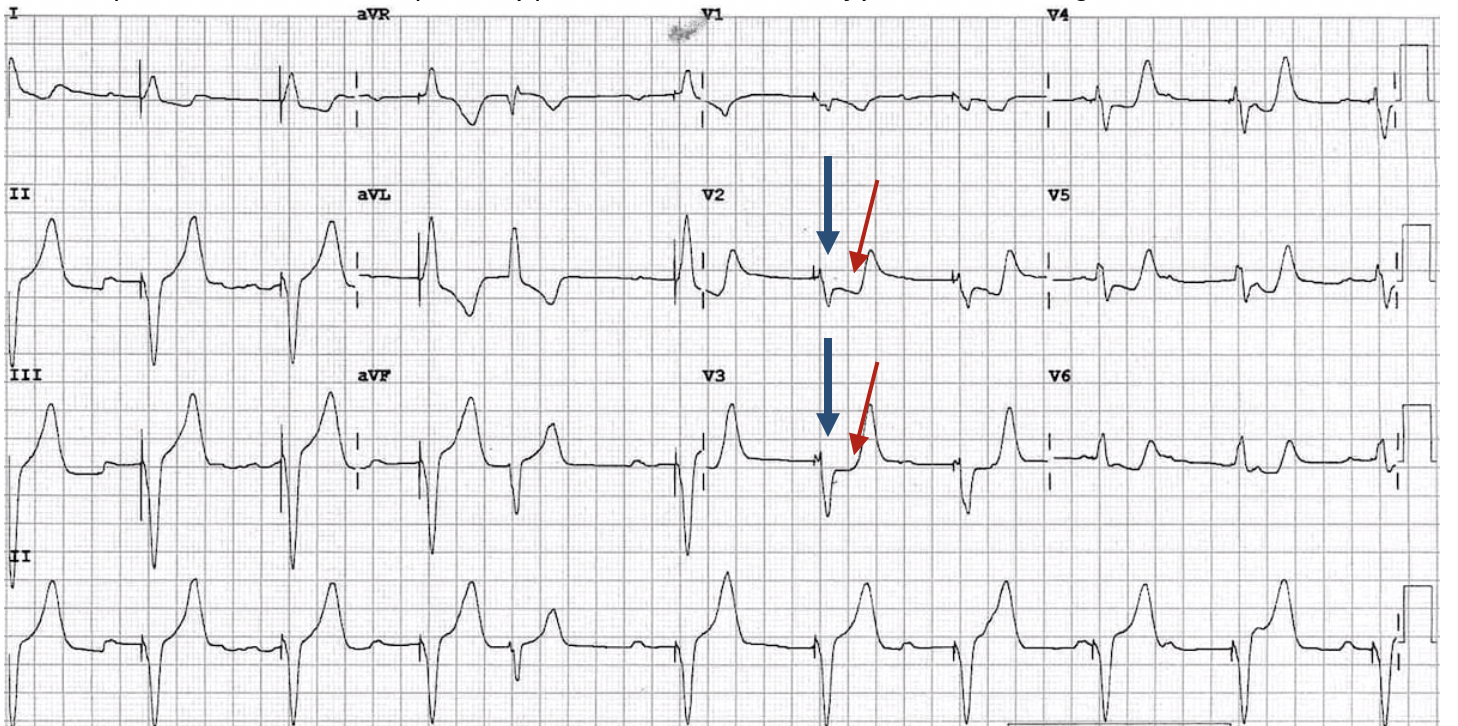

J point ECG Interval • LITFL Medical Blog • ECG Library Basics

Figure 1. Early repolarization pattern on ECG. Note the endQRS nothes What Is A Borderline Ecg Learn what abnormal ekg results mean and how they can indicate heart problems, such as heart. A bundle branch block is a type of heart rhythm disorder that affects the electrical activity of the heart. What does borderline mean on ecg? An electrocardiogram (ekg) measures your heart's electrical activity. It records the electrical signals in the heart. A borderline ecg. What Is A Borderline Ecg.